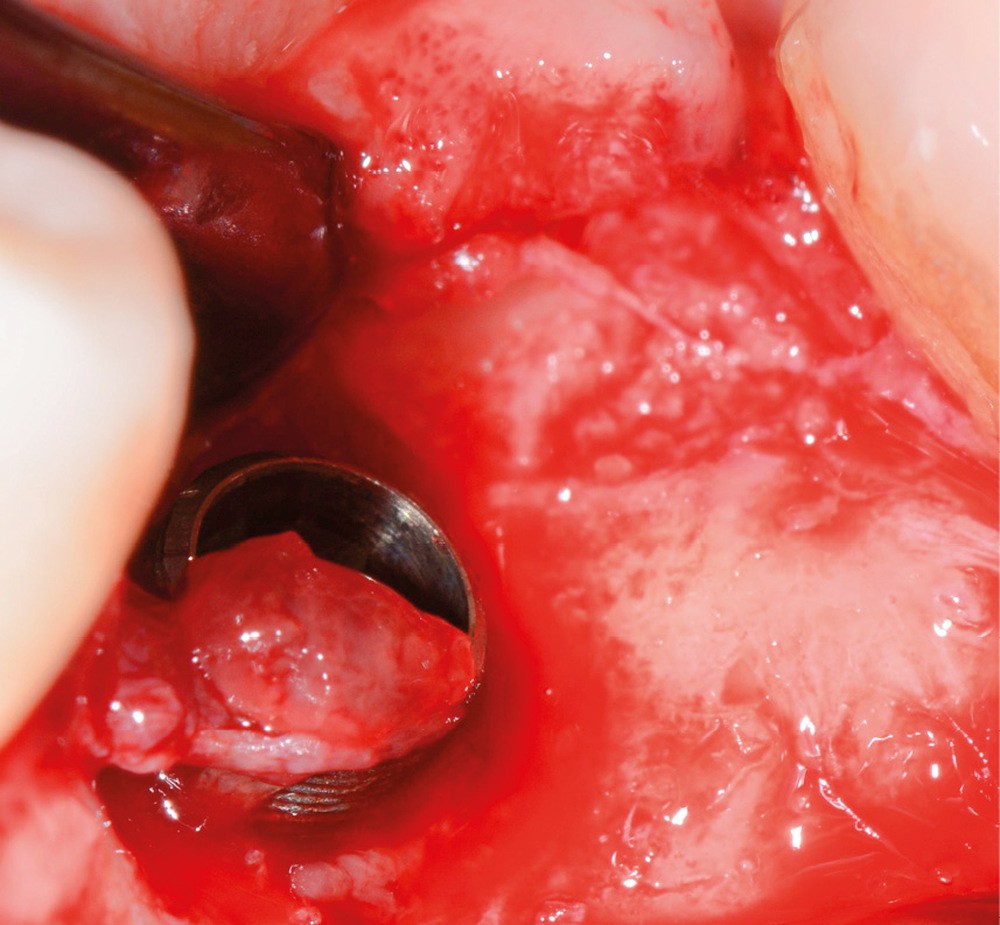

- Avulsion de la 36 et régénération osseuse guidée (ROG) réalisée en 2017 suite à une fracture de la dent et une infection

Chez ce patient, le traitement de la péri-implantite a comporté une chirurgie associant décontamination électrolytique de la surface implantaire, régénération osseuse guidée et enfouissement de l’implant. Le résultat à 2 ans est très moyen au vu du pourcentage de régénération osseuse obtenu. Comment peut-on prévoir un tel résultat alors que l’on a suivi les recommandations à la lettre, que l’on a utilisé les dernières technologies de décontamination, que l’on y a mis tous les moyens, que le patient est en bonne santé générale et qu’il vient en plus régulièrement aux séances de thérapeutique de soutien ? Le succès du traitement des péri-implantites n’est pas simple à obtenir, surtout quand un élément clé est compromis… la maintenance personnelle ! En effet le succès n’est possible que si le contrôle de plaque quotidien est optimal et, ici, ça n’était pas le cas. Le patient se brossait certes les dents, mais ne passait pas quotidiennement les brossettes, ce qui…